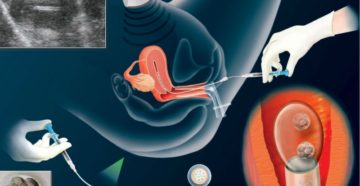

Имплантация эмбриона: основные симптомы и ощущения после прикрепления плодного яйца Большая часть женских познаний о…